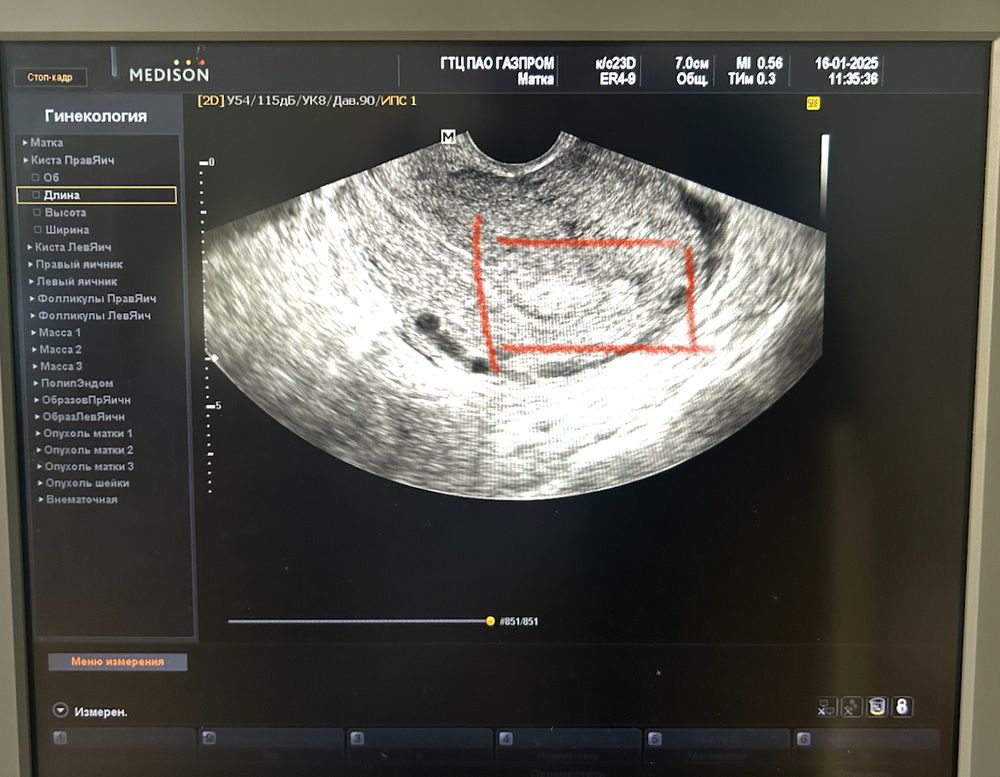

Не дождалась🩸 и сделала узи.

Месяц после искусственных родов на 22 недели.

Не знаю, что меня так спонтанно дернуло, поехала сделала узи,

🥚 киста в правом яичнике 2,5 см

И не понравилось ему что-то в матке, говорит «вот тут видно что-то, контур, полип возможно» 🤔

Ну сказал не переживать , это может «последствия родов еще»и приходить после месячных 🩸